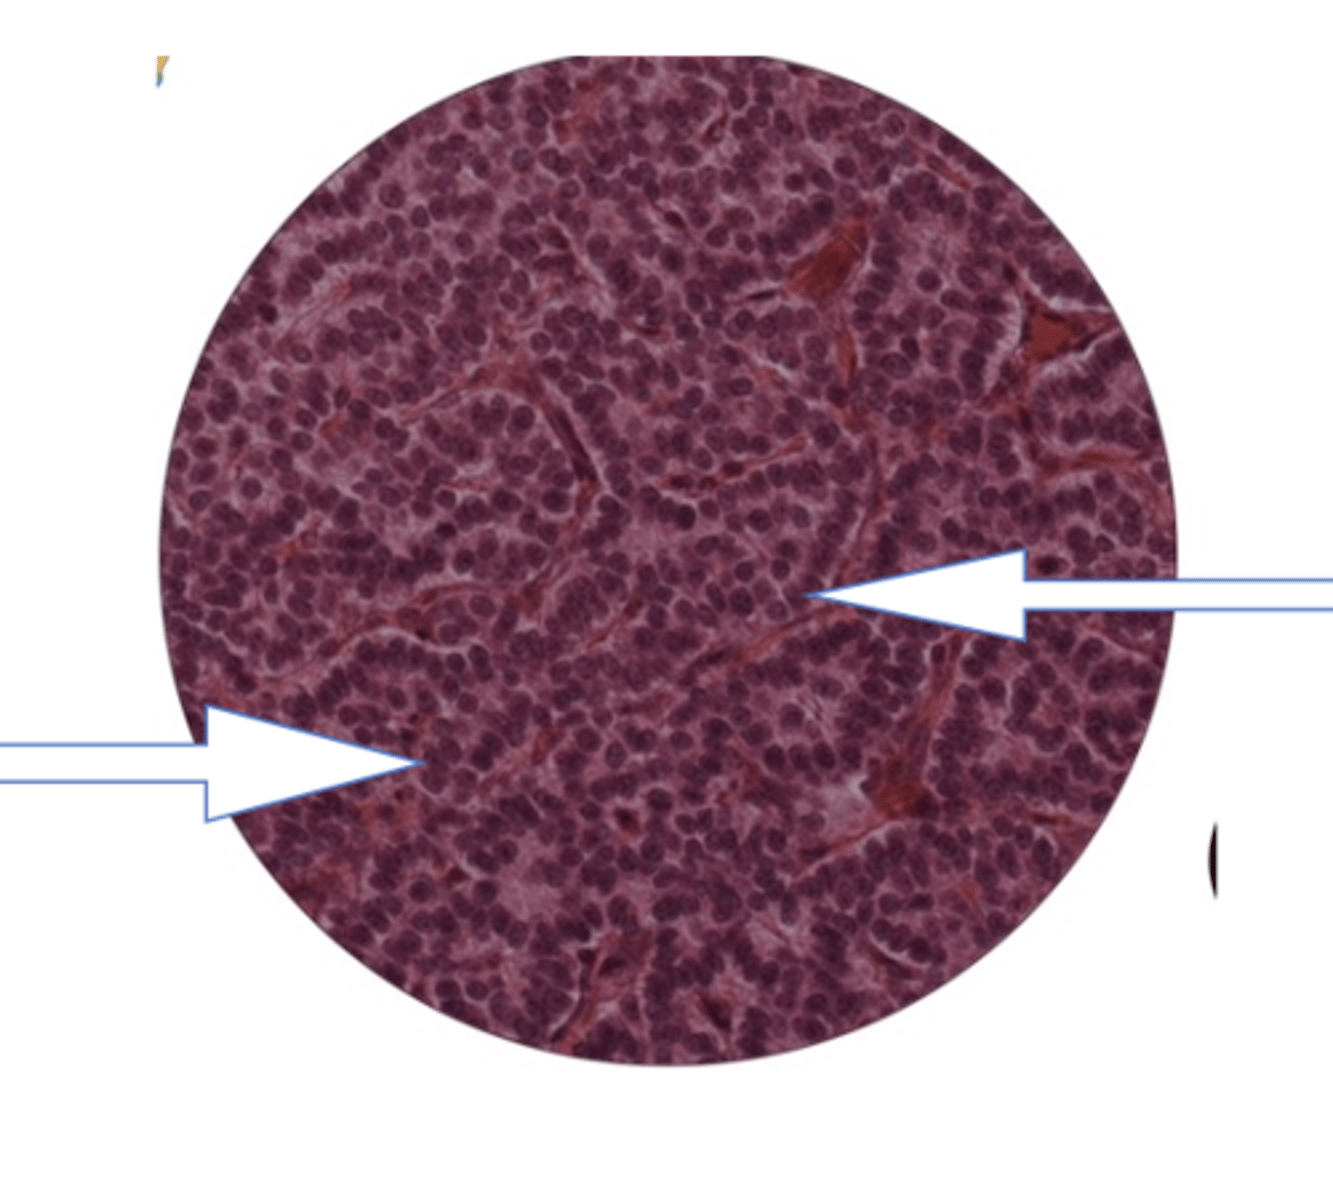

liver lobule

central vein of liver lobule